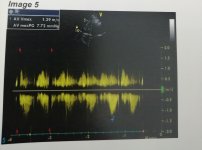

عملت ايكو هل في حاجه في الايكو تستدعي الذهاب لطبيب قلب و ارجو شرحها ان وجدت؟ و شكرا

عملت ايكو هل في حاجه في الايكو تستدعي الذهاب لطبيب قلب و ارجو شرحها ان وجدت؟ و شكرا